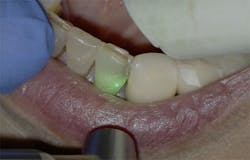

Figure 9: Initial presentation prior to crown lengthening

Figure 10: Immediate post-op hard- and soft-tissue crown lengthening with laser